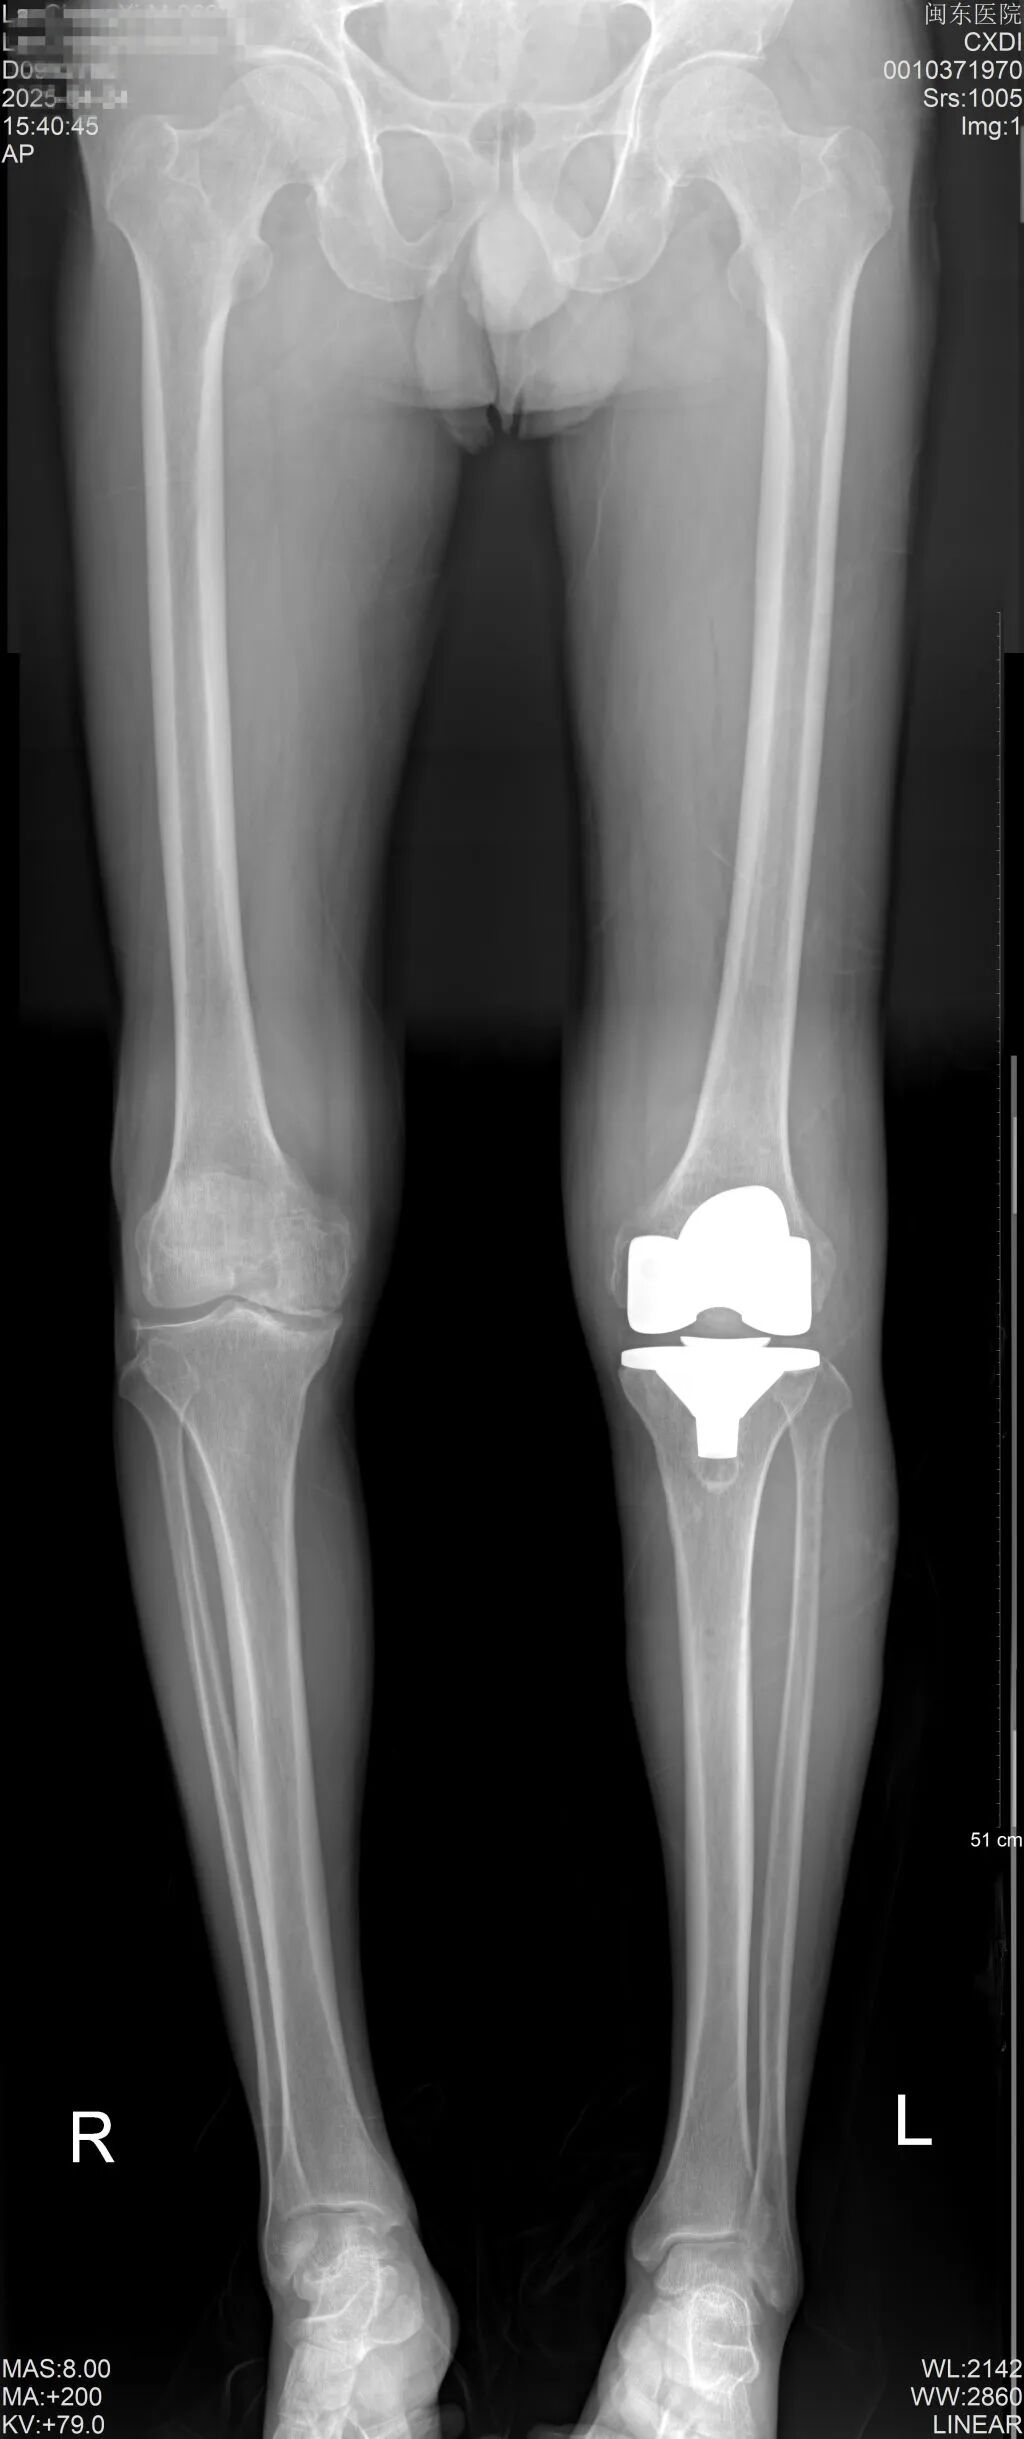

“該系統(tǒng)實(shí)現(xiàn)了四大革命性優(yōu)勢。”王旭介紹說道,一是精準(zhǔn)規(guī)劃,量身定制。突破傳統(tǒng)X線二維評估局限,機(jī)器人通過術(shù)前CT掃描數(shù)據(jù),構(gòu)建出患者膝關(guān)節(jié)的三維模型,智能生成個(gè)性化手術(shù)方案。專家團(tuán)隊(duì)可結(jié)合患者解剖特征進(jìn)行動態(tài)調(diào)整,精確設(shè)定假體的位置、角度和大小,確保假體匹配度達(dá)到“毫米級”精度,真正實(shí)現(xiàn)“一人一策”的精準(zhǔn)醫(yī)療;二是智能導(dǎo)航,誤差可控。在AI導(dǎo)航系統(tǒng)護(hù)航下,機(jī)械臂可精確執(zhí)行0.1毫米級截骨操作,較傳統(tǒng)手術(shù)更加地精準(zhǔn)。獨(dú)有的安全截骨區(qū)間控制系統(tǒng),能在操作偏移時(shí)0.01秒內(nèi)自動制動,徹底規(guī)避血管神經(jīng)損傷風(fēng)險(xiǎn);三是安全升級,全程護(hù)航。創(chuàng)新“無接觸”截骨技術(shù)免除人工拉鉤暴露,結(jié)合多模態(tài)預(yù)警系統(tǒng),大大降低韌帶損傷等并發(fā)癥發(fā)生率,較傳統(tǒng)術(shù)式安全性顯著提升;四是微創(chuàng)革新,加速康復(fù)。摒棄傳統(tǒng)開髓定位方式,通過智能覆蓋算法使假體與骨面完美契合,可以極大的減少患者出血,也避免周圍軟組織的激惹,這些均可促進(jìn)患者術(shù)后康復(fù)。